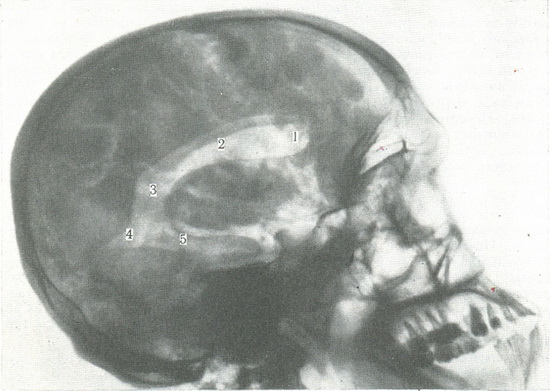

511. Бічна пневмоэнцефалограмма.

1 - передній ріг бічного шлуночка; 2 - тіло бічного шлуночка; 3 - трикутник шлуночка; 4 - задній ріг бічного шлуночка; 5 - нижній ріг бічного шлуночка мозку.

Пневмоенцефалографія - дослідження форми шлуночків мозку і субарахноїдального простору шляхом введення для контрасту повітря або газоподібного кисню в субарахноїдальний простір спинного мозку. Для цього попередньо беруть 5-10 мл спинномозкової рідини. Прицільні оглядові знімки роблять в лобової, потиличної і бічній проекціях. При достатньому заповнення повітрям світлі тіні шлуночків чітко видно на тлі кісток черепа (рис. 511). В потиличній проекції по середній лінії видно III шлуночок, а вище і дещо латеральніше - бічні шлуночки. В лобовій проекції видно чіткі та рівні контури бічних шлуночків у формі симетричних дуг. На бічному знімку контуріруются передні, задні і нижні роги бічних шлуночків. При патологічних станах (пухлина, спайка, гідроцефалія) відзначається зміна контурів, форми і величини шлуночків, їх зміщення.

В першу чергу в субарахноїдальному просторі виявляються цистерни довгастого мозку, мозкового мосту, межножковая, перекреста зорового нерва і цистерна біля великої вени мозку. Повітря в субарахноїдальному просторі півкулі мозку заповнює простір в борознах лобової, тім'яної часток і щілини над мозолистим тілом. Не заповнене повітрям субарахноїдальний простір свідчить про сращениях, його розширення - про зовнішньої гідроцефалії.